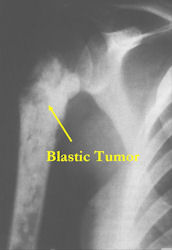

There are 3 radiographic presentations for osteosarcomas, depending upon the amount of osteoid/ossification and calcium deposition:

- Mixed sclerotic and lytic, permeative lesion most common radiographic presentation

- Purely osteoblastic, permeative lesion: dense sclerosis and osteoid production

- Purely lytic, permeative lesion: little osteoid production and/or minimal calcium deposition in osteoid

Conventional osteosarcomas are permeative lesions on plain radiographs (borders of the lesion cannot be clearly delineated)

- Wide zone of transition from lytic/sclerotic areas of tumor to normal bone

- Makes borders of lesion hard to define